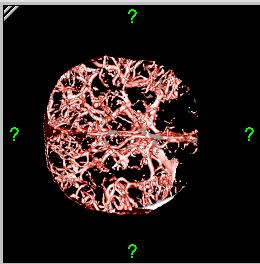

Brain vessels reconstructed in 3D after bone has been removed by segmentation